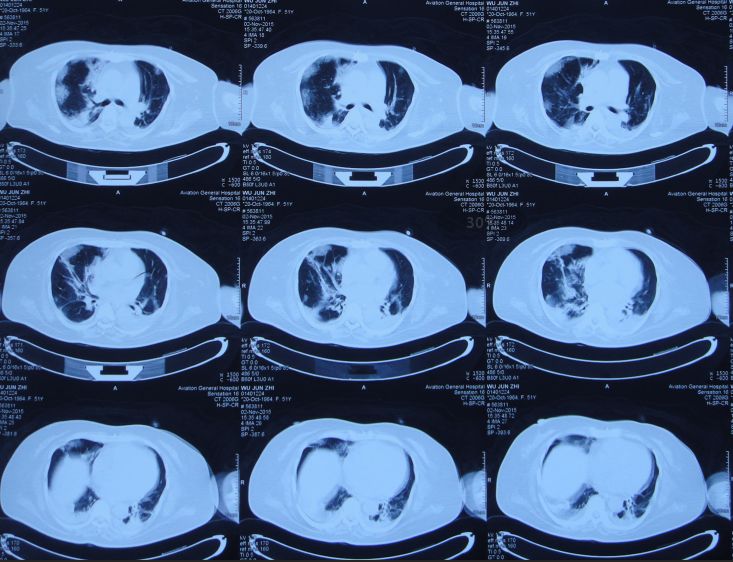

胆囊造瘘术后第3天即2015年11月2日,患者神志朦胧,发热,最高T39.0℃;查胸CT:双肺感染(图36)。查腹部CT:胆囊造瘘术后改变,胆囊较术前缩小,无结石影(图37)。

图36:2015年11月2日胸CT:双肺感染

普外科会诊,考虑患者胆囊周围仍有渗出水肿,可能导致消化道梗阻;并进行了胆囊局部松解引流处理,缓解局部压力。查胸CT:肺部感染伴右侧胸腔积液(图40),给予对症处理。

图40:2015年11月16日胸CT:肺部感染伴右侧胸腔积液